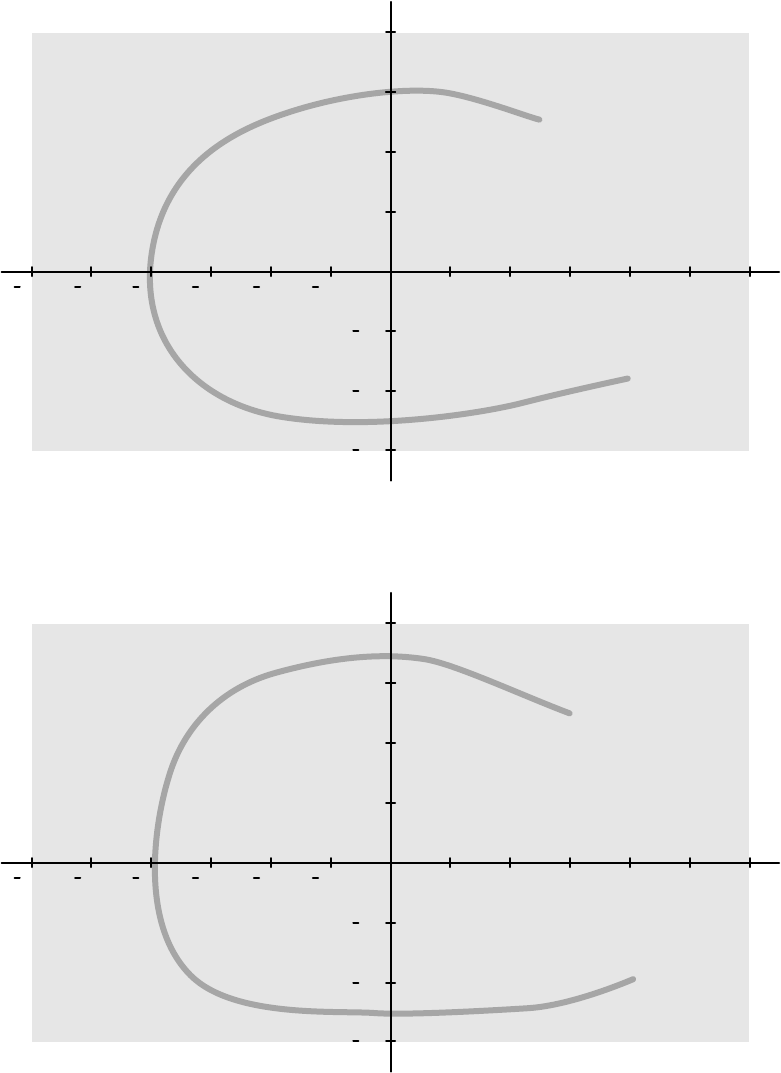

16.21.2 Mapy izokermy systemu C12/F12........................................................................ 310

16.21.3 Mapy izokermy systemu F15................................................................................ 311

16.21.4 Mapy izokermy systemu C20/F20........................................................................ 312